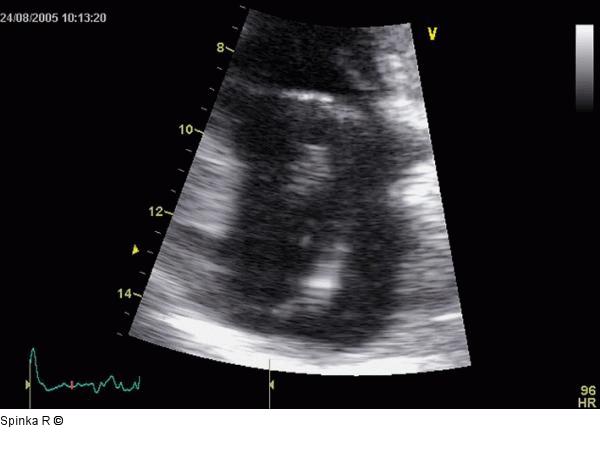

Abbildung 4: Rechtsatriale Thrombose nach 2-Kammer-Schrittmacherimplantation Transthorakale Darstellung der regressiven Veränderung nach mehrwöchiger Therapie mit oralen Antikoagulantien. |

Abbildung 4: Rechtsatriale Thrombose nach 2-Kammer-Schrittmacherimplantation

Transthorakale Darstellung der regressiven Veränderung nach mehrwöchiger Therapie mit oralen Antikoagulantien. |